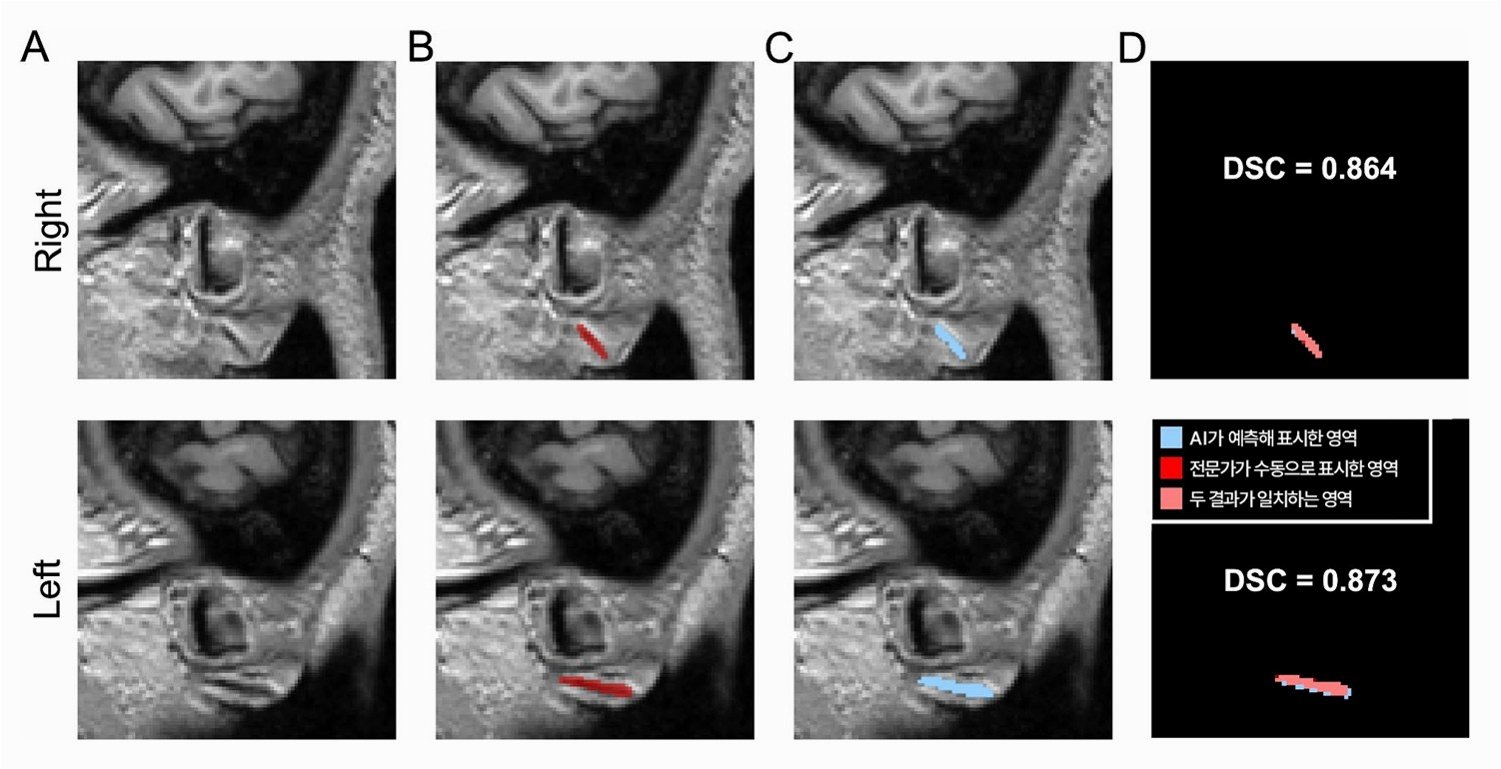

뇌 자기공명영상(MRI)을 단 몇 초 만에 분석하여 신경 질환을 97.5%의 정확도로 진단하고, 환자의 긴급 치료 필요성을 예측하는 혁신적인 인공지능(AI) 기반 모델 '프리마(Prima)'가 개발되었습니다. 이 기술은 영상 검사 즉시 환자에게 피드백을 제공하며, 진단된 질환에 따라 최적의 세부 전문의에게 알림을 추천하는 기능까지 갖추고 있습니다미국 미시간대 의대 토드 홀런 교수팀이 네이처 바이오메디컬 엔지니어링에 발표한 이 연구는 신경영상 분야에 획기적인 변화를 가져올 것으로 기대됩니다.

매년 수백만 건의 MRI 검사가 시행되지만, 인력 부족과 진단 오류 등의 문제가 발생하고 있습니다프리마는 기존 AI 모델과 달리, 특정 과제에 국한된 데이터가 아닌 미시간대에서 축적된 20여만 건의 MRI 검사와 560만 개의 영상 시퀀스 등 수십 년간의 방대한 디지털 영상의학 자료를 학습했습니다. 이러한 학습을 통해 프리마는 1년간 3만여 건의 MRI 검사를 이용한 시험에서 수 초 만에 신경계 질환을 97.5%의 정확도로 진단하는 놀라운 성능을 입증했습니다.

논문의 제1 저자인 이웨이 뤼 박사는 "뇌 MRI 판독 시 정확성만큼이나 신속한 판독이 적시 진단과 치료 성과 향상에 매우 중요하다"고 강조했습니다프리마는 여러 핵심 단계에서 정확성을 희생하지 않으면서 임상 진료를 효율화할 수 있음을 보여주며, 빠르고 정확한 정보 제공을 통해 의사와 의료 시스템의 부담을 줄여줄 잠재력을 지니고 있습니다.